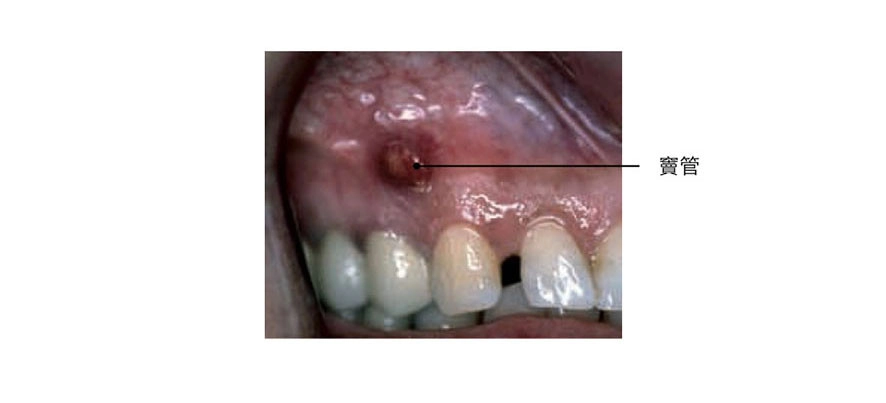

若牙根尖感染較為嚴重,導致根尖周圍組織因細菌作用下,發生壞死、溶解形成膿液,則稱為齒槽膿腫,此時牙齒周圍可能會有脹痛感,但若膿液經由牙齦處形成的竇管排出時,症狀可能會緩解。